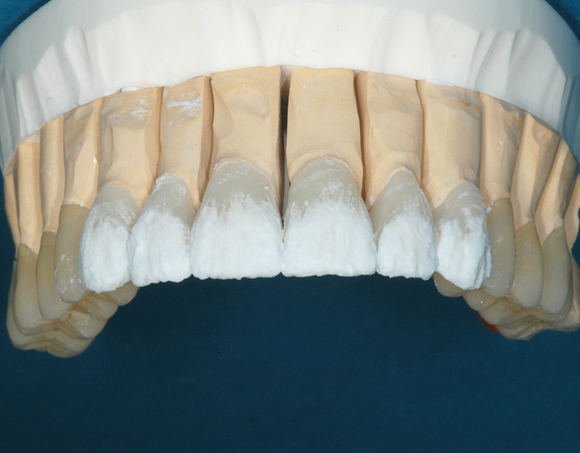

22 Einzelkronen mit Eris for E II

Empress II Presskeramik mit Eris Verblendkeramik bei einer Neuversorgung im Oberkiefer komplett und im Unterkiefer Vollkronen auf den Seitenzähnen.

Ein Projekt aus dem Jahr 2004

Hier wurden der ganze Oberkiefer und die Seitenzähne im Unterkiefer mit neuen Kronen aus Empress 2 und mit Eris Verblendkeramik versorgt.